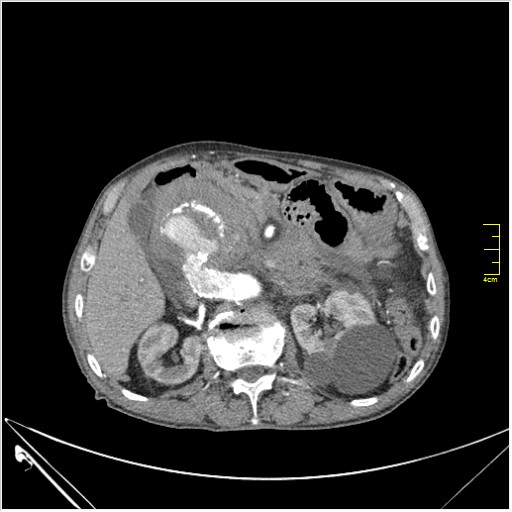

Пациент Т. 64 года, обратился на КТ брюшной полости амбулаторно (!), по направлению семейного врача с диагнозом abdominal mass, буквально: образование брюшной полости.

Huge abdominal aorta aneurism. Simple renal cortical cysts (Bosniak type 1).